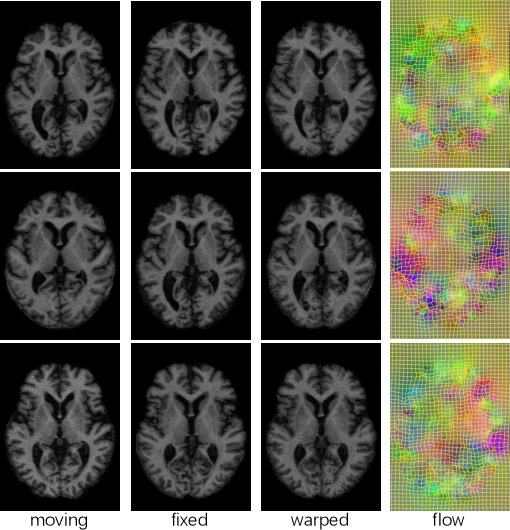

Abstract:Deep learning-based deformable registration methods have been widely investigated in diverse medical applications. Learning-based deformable registration relies on weighted objective functions trading off registration accuracy and smoothness of the deformation field. Therefore, they inevitably require tuning the hyperparameter for optimal registration performance. Tuning the hyperparameters is highly computationally expensive and introduces undesired dependencies on domain knowledge. In this study, we construct a registration model based on the gradient surgery mechanism, named GSMorph, to achieve a hyperparameter-free balance on multiple losses. In GSMorph, we reformulate the optimization procedure by projecting the gradient of similarity loss orthogonally to the plane associated with the smoothness constraint, rather than additionally introducing a hyperparameter to balance these two competing terms. Furthermore, our method is model-agnostic and can be merged into any deep registration network without introducing extra parameters or slowing down inference. In this study, We compared our method with state-of-the-art (SOTA) deformable registration approaches over two publicly available cardiac MRI datasets. GSMorph proves superior to five SOTA learning-based registration models and two conventional registration techniques, SyN and Demons, on both registration accuracy and smoothness.

Abstract:We learn a deformable registration model for T1-weighted MR images by considering multiple image characteristics via a hybrid loss. Our method registers the OASIS dataset with high accuracy while preserving deformation smoothness.

Abstract:Deformable image registration is fundamental to longitudinal and population analysis. Geometric alignment of the infant brain MR images is challenging, owing to rapid changes in image appearance in association with brain development. In this paper, we propose an infant-dedicated deep registration network that uses the auto-context strategy to gradually refine the deformation fields to obtain highly accurate correspondences. Instead of training multiple registration networks, our method estimates the deformation fields by invoking a single network multiple times for iterative deformation refinement. The final deformation field is obtained by the incremental composition of the deformation fields. Experimental results in comparison with state-of-the-art registration methods indicate that our method achieves higher accuracy while at the same time preserves the smoothness of the deformation fields. Our implementation is available online.